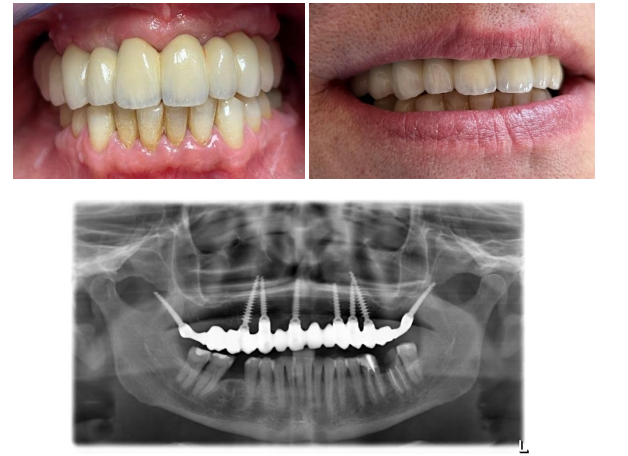

Three weeks after initial consultation, patient´s mouth was rehabilitated with definitive metal ceramic bridges. This was made possible due to the achieved bicortical anchorage in the anterior part and a strong cortical anchorage at the pterygoid plates  (75 N/cm) in the maxilla,  these anchorage ensured high primary stability which encourages immediate loading. Fig 5

Figure 5: Clinical photograph and the panoramic radiograph of patient and after bridge delivery, day of placement

A metal ceramic bridge was fabricated after frame try-in. Three weeks after the beginning of the treatment, the gum has healed nicely, bridge was screw-retained with angulated screw channels so as to get a perfect fit fig 10.

Figure 10

Figure 5